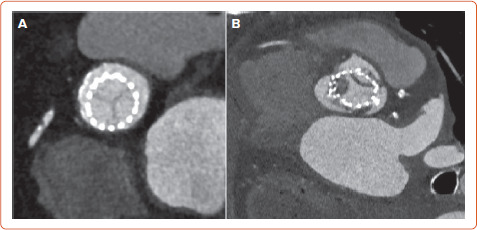

近年来,经导管主动脉瓣植入术患者发生亚临床小叶血栓形成(SLT)的现象越来越重要。CT诊断的低衰减小叶增厚和影响运动的低衰减是SLT的标志,其发生率随筛查强度而变化。这些现象是否代表小叶血栓形成,降低瓣膜耐久性和增加中风风险仍然是一个有争议的问题。TAVI后的最佳抗血栓治疗仍不确定,最佳治疗策略仍未确定。正在进行和未来的试验将为预防和治疗SLT的最佳策略提供更多证据。

In recent years, the phenomenon of subclinical leaflet thrombosis (SLT) in patients who have undergone transcatheter aortic valve implantation has become increasingly relevant. Hypo-attenuating leaflet thickening and hypo-attenuation affecting motion diagnosed by CT are the hallmarks of SLT, and their incidence varies depending on the intensity of screening. Whether these phenomena are a surrogate for leaflet thrombosis reducing valve durability and increasing the risk of stroke is still a matter of debate. Uncertainty remains over the optimal antithrombotic therapy after TAVI and the best treatment strategy is still not confirmed. Ongoing and future trials will provide more evidence about the best strategy for the prevention and treatment of SLT.